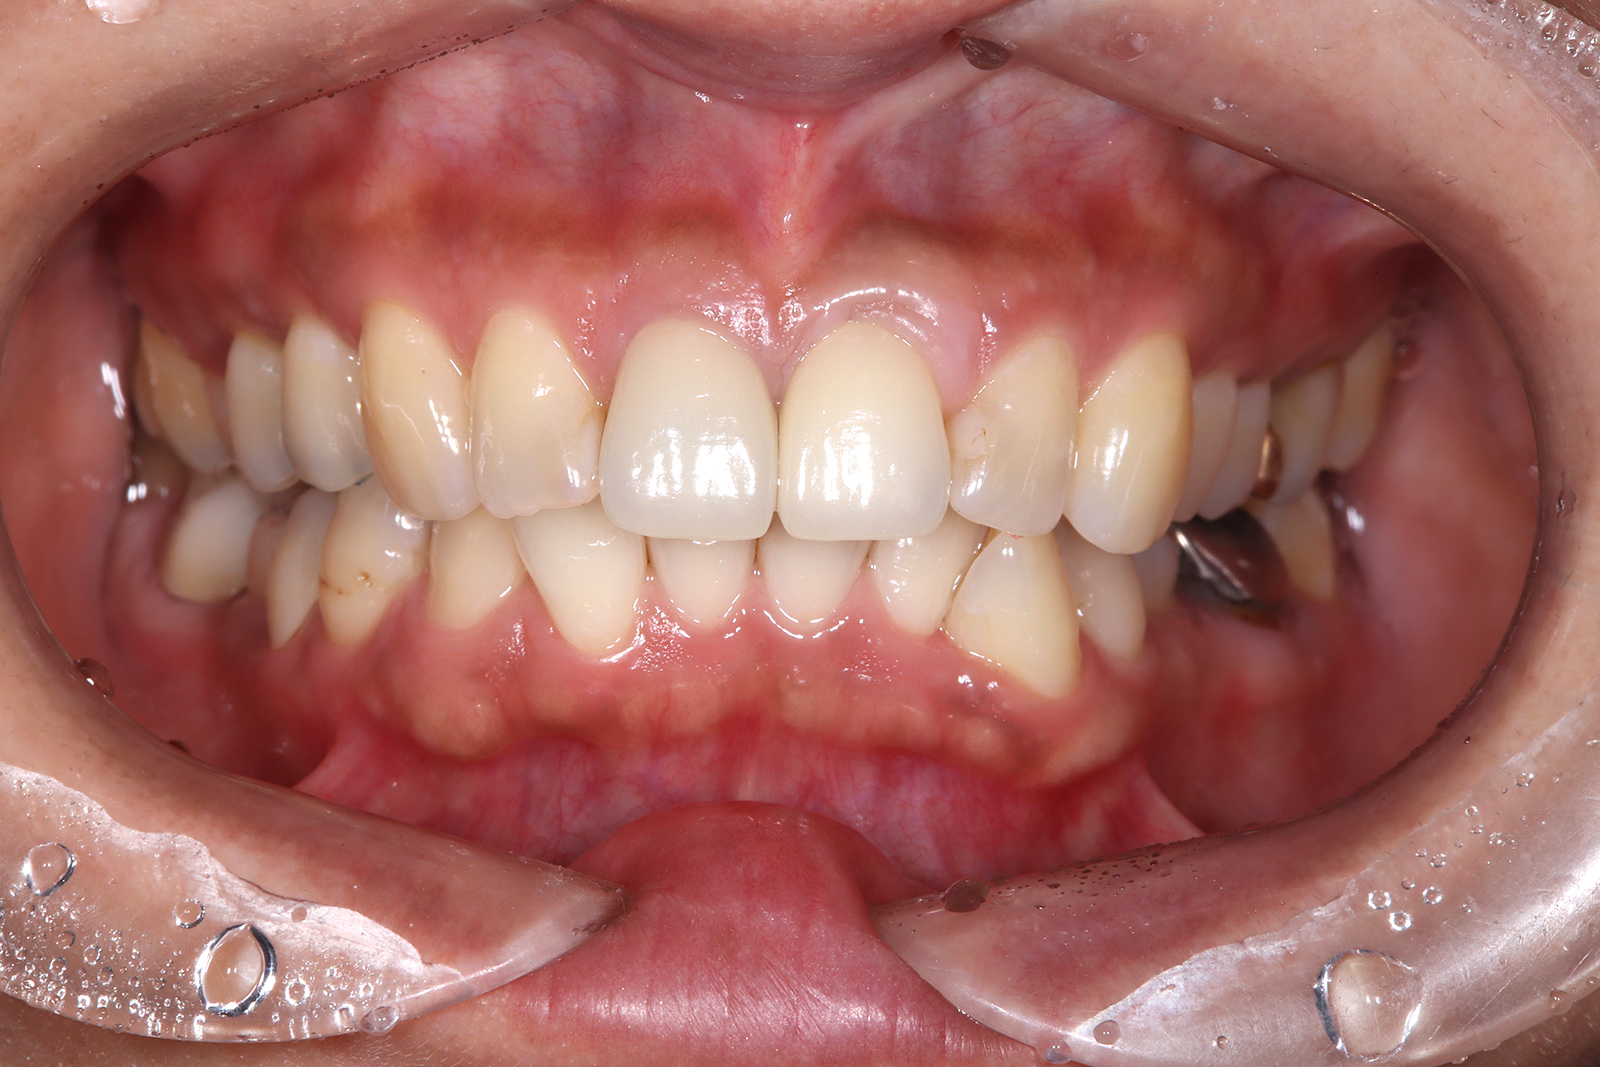

• 治療前

• 治療後

向かって右側の上あご前歯に、抜歯即時荷重によるインプラント治療を行った。

治療期間は1年で、費用は60万円ほど。

定期的なメンテナンスを行わないと、インプラント周囲炎のリスクがある。

向かって右側の上あご前歯に、抜歯即時荷重によるインプラント治療を行った。治療期間は1年で、費用は60万円ほど。定期的なメンテナンスを行わないと、インプラント周囲炎のリスクがある。